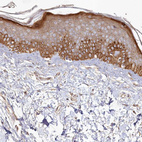

Immunohistochemical staining of human cerebral cortex, liver, skin and testis using Anti-HAL antibody HPA038547 (A) shows similar protein distribution across tissues to independent antibody HPA038548 (B).